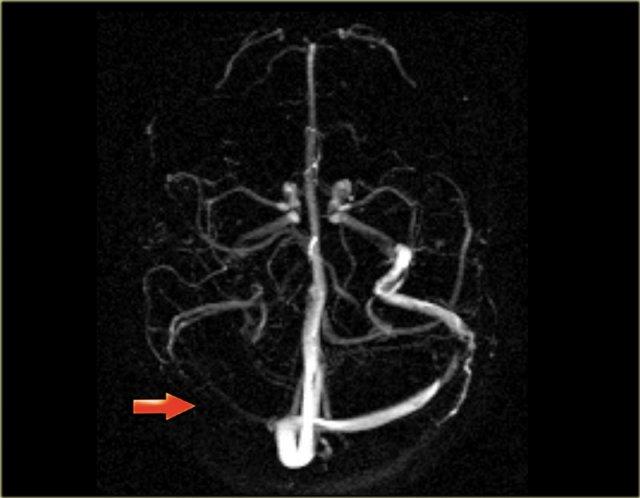

Hình ảnh MIP cắt ngang của chụp mạch máu tương phản pha. Xoang ngang và tĩnh mạch cảnh trong bên phải không có tín hiệu do huyết khối.

Bên trái là hình ảnh MIP theo mặt phẳng đứng dọc và chếch của một ca chụp tĩnh mạch MR có tiêm thuốc tương phản từ bình thường.

Lưu ý tĩnh mạch Trolard nổi bật (mũi tên đỏ) và tĩnh mạch Labbe (mũi tên xanh lam).